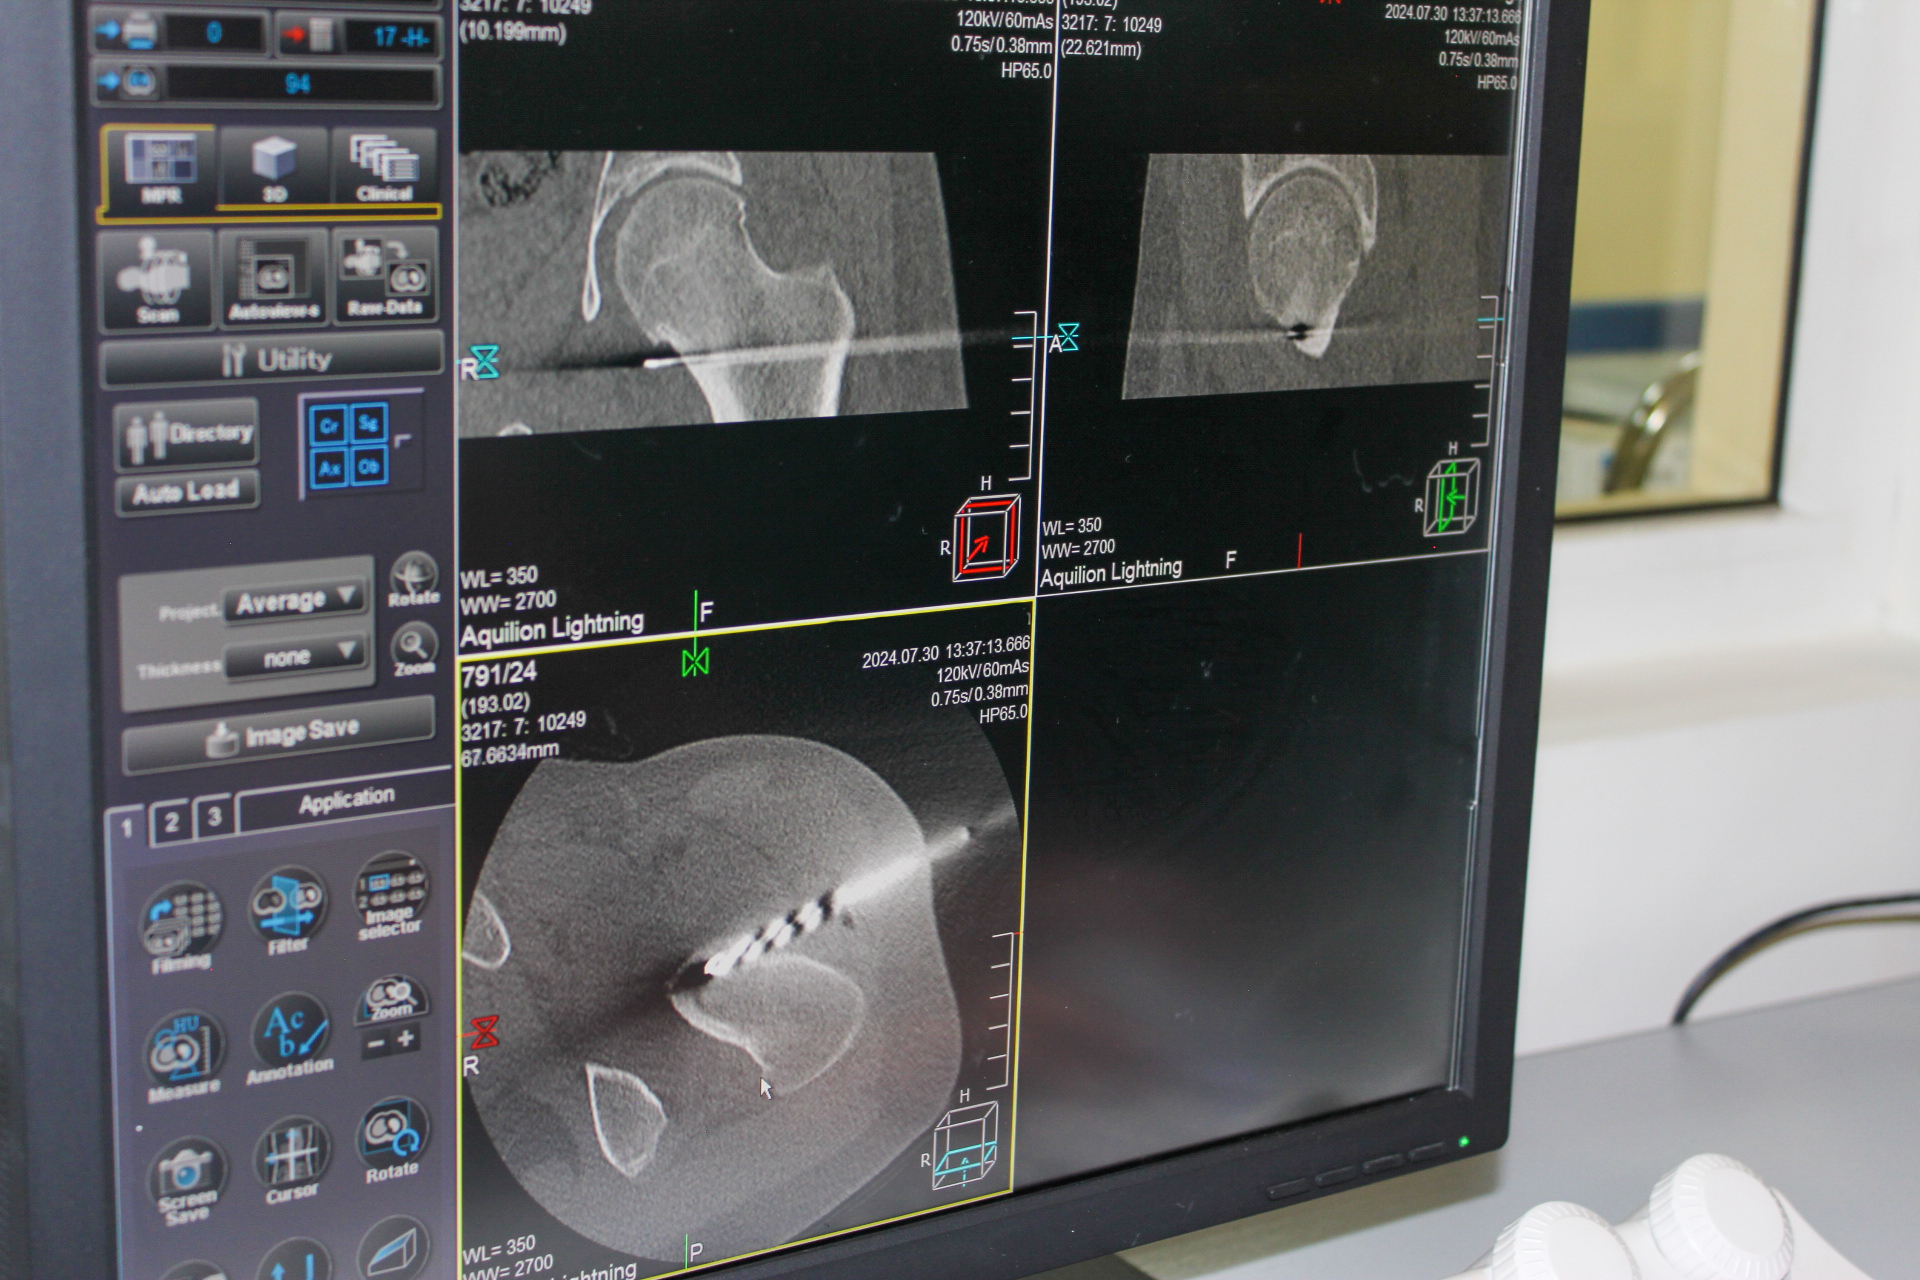

A 17-year-old patient had been complaining of pain in the left hip joint for three years and recently started limping. He had undergone several examinations and, as usual, consulted a rheumatologist, receiving treatment for hip osteoarthritis. However, as the treatment showed no effectiveness, the patient was referred to the "Arabkir" Medical Center for an orthopedic consultation. The orthopedic team suspected osteoid osteoma and ordered a computed tomography (CT) scan, which confirmed the presence of osteoid osteoma located in the neck of the femur.

To alleviate the pain significantly impacting the patient's quality of life, a surgical intervention was planned under computed tomography guidance. This technique allowed the surgical team to identify the shortest, least traumatic, and most effective path for surgical instruments to access the osteoma without damaging other important anatomical structures.

After carefully selecting the optimal access point, the orthopedic surgeon inserted a metal guide wire into the pathological focus, made a small 1 cm incision at the entry point, and completely excised the osteoma using a special scalpel. The entire procedure was monitored in real-time by a radiologist who reviewed the CT images.